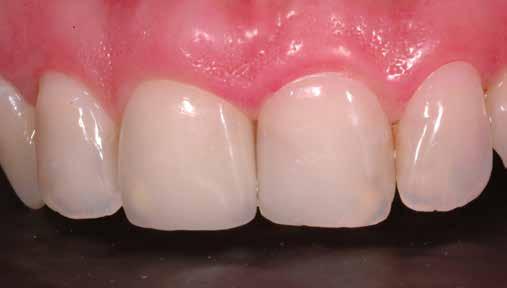

A 2020 januárjában elkezdett kezeléssorozat befejezését az év márciusában, hazánkba is begyűrűző Covid-19 pandémia késleltette, így kb. 6 hónap gyógyulás után láttunk hozzá az emergencia profil és a gingivális zenit ideiglenes koronával történő formázásához (11. és 12. kép). A 3 hetente végzett apró alakításokkal sikerült megfelelő ínyprofilt kialakítani, a „rózsaszín esztétika” a páciens számára is megfelelő volt. A bal felső nagymetsző fog meziális kompozit tömés cseréjét követően, individualizált nyitott kanalas lenyomati fejet készítettünk: az akrilát ideiglenes korona profilját átlátszó szilikonnal lemásoltuk, majd a körszimmetrikus gyári lenyomati fej és az ideiglenes korona kontúrja közötti hézagot folyékony kompozittal töltöttük ki (13. kép). Az így készített egyéni lenyomati fejjel vettünk lenyomatot a végleges, kerámialeplezésű cirkónium-dioxid vázas, átmenő csavaros rögzítésű koronához. (A fogtechnikai munkát Nébl Péter fogtechnikusmester készítette.), (14., 15., 16 és 17. képek).

A kész korona átadásakor a páciens elégedett volt az esztétikával, az azóta eltelt évben rendszeres kontrollokon jelent meg, melyek során meggyőződtünk a kemény- és lágyszövetek stabilitásáról (18. és 19. képek).

17. a–b képek: A kész munka átadáskor. 18. a–c képek: 1 éves kontroll. 19. kép: Intraorális kontroll röntgen felvétele 1 évvel az átadás után.